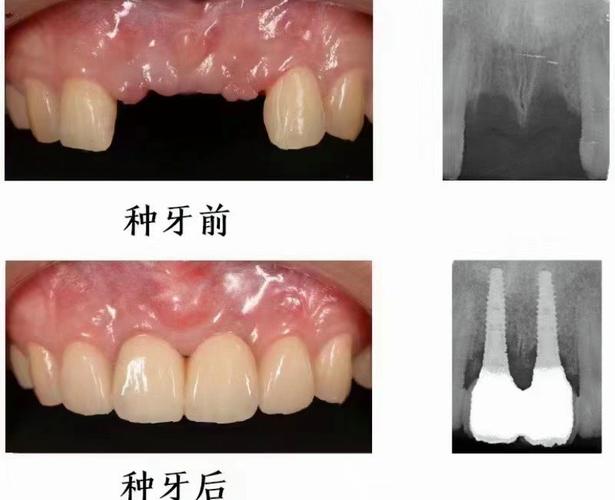

在合肥,随着口腔健康意识的提升,种植牙已成为缺牙修复的主流选择,但面对众多机构和宣传,不少市民会困惑“合肥种牙哪里好”。“好”的标准因人而异,需结合医生资质、设备技术、价格透明度、服务体验等多维度综合考量,本文将从合肥种牙的主要选择方向、关键考量因素、推荐机构类型及价格参考等方面展开详细分析,助您找到适合自己的种牙方案。

设备与技术:种植牙需依赖先进设备辅助,如CBCT(可三维扫描牙槽骨,精准判断骨量、密度、神经血管位置)、数字化种植导板(实现精准定位,减少创伤)、无菌手术室(避免感染),目前主流技术有微创种植、即刻种植、即刻负重(种牙后当天戴牙)、All-on-4半口/全口种植等,可根据自身需求和经济能力选择。